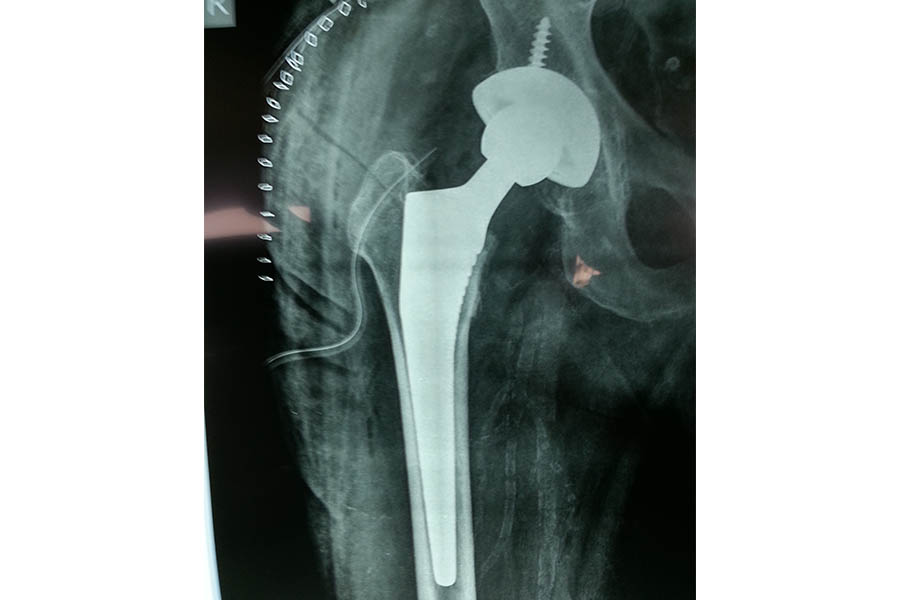

Total Hip Replacement

Difficult Replacement

Case 1